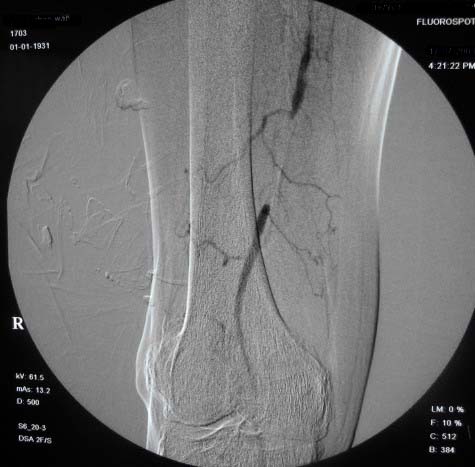

右下肢:

右侧股浅动脉上、中段多处狭窄,下段闭塞。左侧股浅动脉多处狭窄,国动脉起始部狭窄。可以用球囊扩张配合动脉内溶栓或股浅动脉支架置入。多为糖尿病所致。

双侧股动脉及腘动脉多发狭窄,右股动脉下段闭塞并侧支形成。病变较广泛,球囊可试试,如病人经济不好,最好还是以药物治疗为主。个人意见。